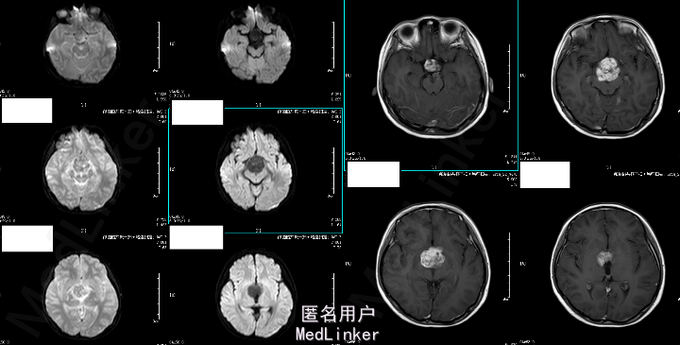

女 11岁 学生 主诉:2014年5月无明显诱因出现头晕,偶有头痛,双眼视力下降,步态正常。外院头颅MRI提示“鞍上占位性病变,累及蝶鞍,多为生殖细胞瘤,不完全除外颅外咽鼓管瘤”。 既往史、个人史、家族史未见异常。

T 36.1℃ P 80bpm,R 20bpm,BP 100/65mmHg。心肺腹未见明显异常。神经查体未见命像一场。 辅助检查:2014-06-20外院头颅MRI:鞍上占位性病变,累及蝶鞍,多为生殖细胞瘤,不完全除外颅外咽鼓管瘤 2014-07-08我院头颅MR增强:鞍区占位性病变,考虑生殖细胞来源的肿瘤可能性大。 b-HCG 13.53ng/ml,AFP 224.84ng/ml。

诊断:鞍上区恶性肿瘤:颅内生殖细胞肿瘤 处理:放疗。(3D-CRT 36GY/FX),胸腺肽增强免疫力及副作用对症处理。 (2015-06-24复查头颅MR结果如下)